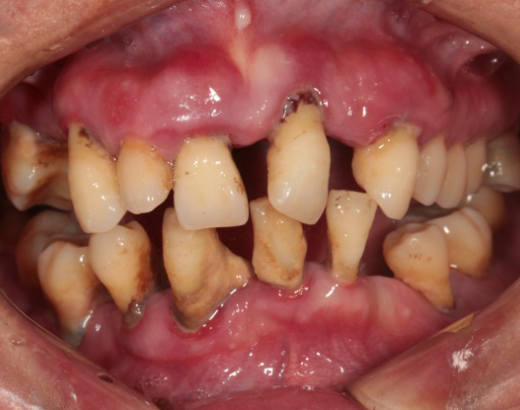

Intraoral Examination(A zone=Right upper jaw、B zone=Left upper jaw、C zone=Left lower jaw、D zone=Right lower jaw)

Poor oral hygiene, accumulation of calculus, three-degree loosening of the entire mouth

Periodontitis causes severe absorption of the upper and lower jaws

A zone A4-A6、B zone B2、C zone C2-C4、D zone D2-D3 lost

A zone A1-A3、A7、B zone B1、B5-B7、C zone C1、C5-C7、D zone D1、D4-D8 all with III°loosen

Photos of preliminary oral diagnosis